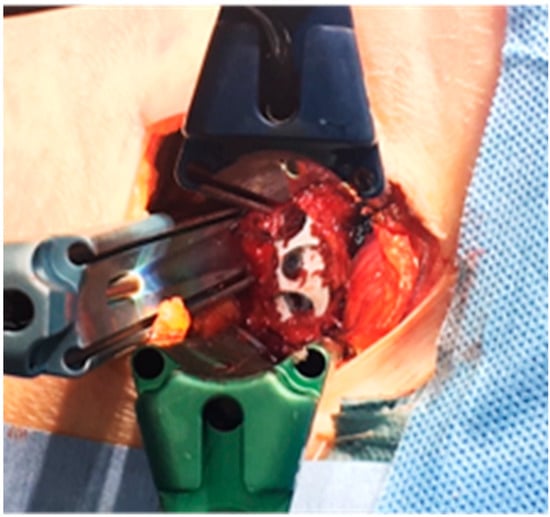

3.1.1. Case 1: 78 Years Old, Female, Degenerative Lumbar Scoliosis

3.1.2. Case 2: 68 Years Old, Female, Adult Scoliosis